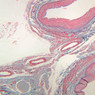

Blood passes from the elastic arteries via arteries of intermediate type into the muscular (distribution) arteries. Locate and examine a muscular artery in slide A-28 (Renal artery & vein, H&E [2.5x, 10x-labeled, 20x, 40x-labeled] [10x-labeled, 20x, 40x]; AF [10x-labeled, 20x, 40x]). Note that the tunica intima is separated from the tunica media by a thick internal elastic membrane which has a scalloped appearance. The tunica media consists of many layers of smooth muscle cells arranged concentrically in a spiral fashion (A-28, H&E [2.5x, 10x-labeled, 20x, 40x] [2.5x, 10x, 20x, 40x, 40x] [2.5x, 10x, 20x]). An external elastic membrane is present, but is thinner and less complete than the internal elastic membrane. The tunica adventitia is about equal in size to the media in this vessel and is more intensely eosinophilic in its staining properties. Note the appearance of small blood vessels in the outer part of the tunica adventitia. You may also be able to see occasional nerve fibers.